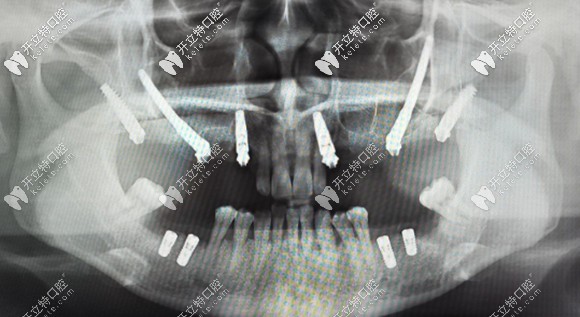

簡單來說,把種植體植入到顴骨和翼板骨上的種植方法,就叫做穿顴穿翼種植技術(shù)。

對于上頜骨切除、上頜骨重度萎縮,做常規(guī)的上頜竇內(nèi)外提升,也沒有辦法達(dá)到種植條件的無牙頜患者,就需要向頜面部的顴骨和翼板找可植入種植體的骨頭。

而這部分的骨頭也適合作為種植位點(diǎn),它不會(huì)像牙槽骨那樣萎縮吸收。但是,也由于這個(gè)位置比較靠上,所以,手術(shù)的難度也就大大增加了,一般的口腔機(jī)構(gòu)都無法進(jìn)行這項(xiàng)手術(shù)。

穿顴穿翼就是種植體植入到顴骨和翼板骨上的種植方法

例如:術(shù)前采用專用軟件,結(jié)合患者口腔數(shù)據(jù),對種植方案進(jìn)行詳細(xì)手術(shù)設(shè)計(jì)。

采用3D打印患者上頜骨模型,在模型上先進(jìn)行摸擬手術(shù)。

制作手術(shù)導(dǎo)板,以便于在手術(shù)中進(jìn)行定點(diǎn)指導(dǎo)等措施。